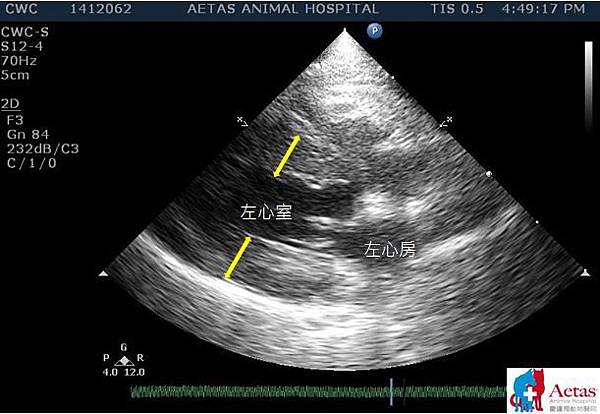

此圖為肥厚性心肌病的貓咪,圖中白色字體標示出左心室跟左心房的位置。兩個黃色雙箭頭的長度則代表了心室壁肌肉的厚度,可以見到其心肌有明顯增厚的傾向,會導致心室舒張期的功能異常。